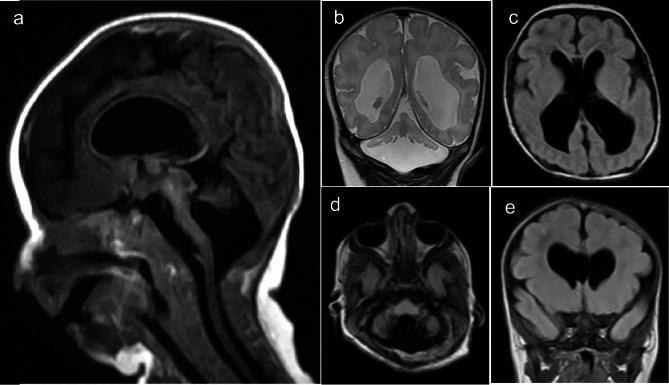

Cerebellar vermis hypoplasia refers to a varying degree of incomplete development of the cerebellum and vermis. A Saudi family with four affected individuals with cerebellar vermis hypoplasia, facial dysmorphology, visual impairment, skeletal, and cardiac abnormalities was ascertained in this study. Three out of four patients could not survive longer and had died in early infancy. Genetic analysis of the youngest affected was performed by genome-wide homozygosity mapping coupled with whole exome sequencing (WES), followed by Sanger validation. Genome-wide genotyping analysis mapped the phenotype to chromosome 8q24.3. Using an autosomal recessive model, considering deleterious variants with minor allele frequency of less than 0.001 in WES data, a homozygous missense variant (NM_025251.2; ARHGAP39; c.1301G > T; p.Cys434Phe) was selected as a potential candidate for the phenotype. The variant (c.1301G > T) in the ARHGAP39 is in the region of homozygosity on chromosome 8q24.3. ARHGAP39 is a Rho GTPase-activating protein 39 and has been known to regulate apoptosis, cell migration, neurogenesis, and cerebral and hippocampal dendritic spine morphology. Mice homozygous for arhgap39 knockouts have shown premature embryonic lethality. Our findings present the first ever human phenotype associated with ARHGAP39 alteration.

小脑蚓部发育不良是指小脑和蚓部的不同程度的不完全发育。本研究中,确定了一个沙特阿拉伯家族中有四个受影响的个体患有小脑蚓部发育不良、面部畸形、视力障碍、骨骼和心脏异常。四个患者中有三个不能存活更长时间,在婴儿早期死亡。对最年轻的受影响者进行了全基因组纯合性作图与外显子组测序(WES)相结合的遗传分析,随后进行了 Sanger 验证。全基因组基因型分析将表型定位到 8q24.3 染色体上。使用常染色体隐性遗传模型,考虑 WES 数据中杂合子频率小于 0.001 的有害变异,选择纯合错义变异(NM_025251.2; ARHGAP39; c.1301G>T; p.Cys434Phe)作为表型的潜在候选者。ARHGAP39 中的变异(c.1301G>T)位于 8q24.3 染色体的纯合区域。ARHGAP39 是一种 Rho GTPase 激活蛋白 39,已知可调节细胞凋亡、细胞迁移、神经发生以及大脑和海马树突棘形态。arhgap39 敲除纯合子小鼠表现出胚胎期过早致死。我们的发现首次提出了与 ARHGAP39 改变相关的人类表型。